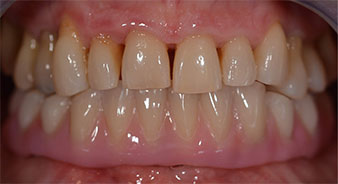

Die 64-jährige Patientin wurde mit einer Unterkiefer-Restbezahnung 38, 33 und 43 und einer klammerbefestigten Interimsprothese im Unterkiefer vorstellig (Abb. 1 und 2).

Im Anschluss erfolgt die Abformung und Bissnahme, sodass die Zahntechniker umgehend mit der Anfertigung der provisorischen Arbeit beginnen können. Diese wird im Anschluss am gleichen Tag eingeschraubt (Abb. 17 und 18).

Nach der Zeit, die für die Osseointegration benötigt wird, kann die endgültige Abformung der Implantate erfolgen und entsprechend die endgültige Arbeit angefertigt werden (Abb. 19 und 20). Hier können Behandler und Patient gemeinsam entscheiden, ob diese eine Keramik- oder Kunststoffverblendung, ein Zirkon- oder Metallgerüst bekommen soll. Im vorliegenden Fall hat sich das Team um Dr. Pascu, aufgrund der unklaren Prognose der Oberkieferbezahnung und des elongierten Zahnes 24, für eine Kunststoffverblendung entschieden. Diese ist im Allgemeinen wesentlich einfacher umzustellen und der neuen Situation im Oberkiefer anzupassen.